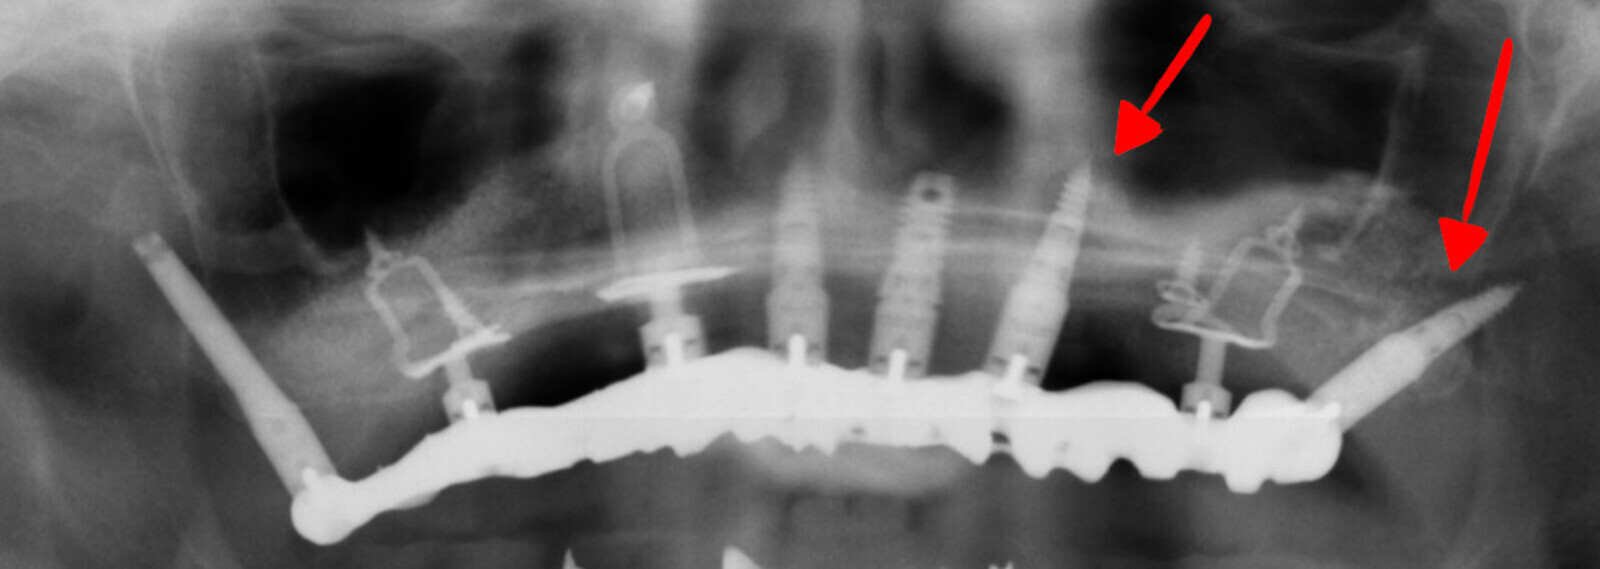

Fig. 6 : Illustration d’un cas ou les implants ont été placés au fur et à mesure de l’amélioration de la densité osseuse.